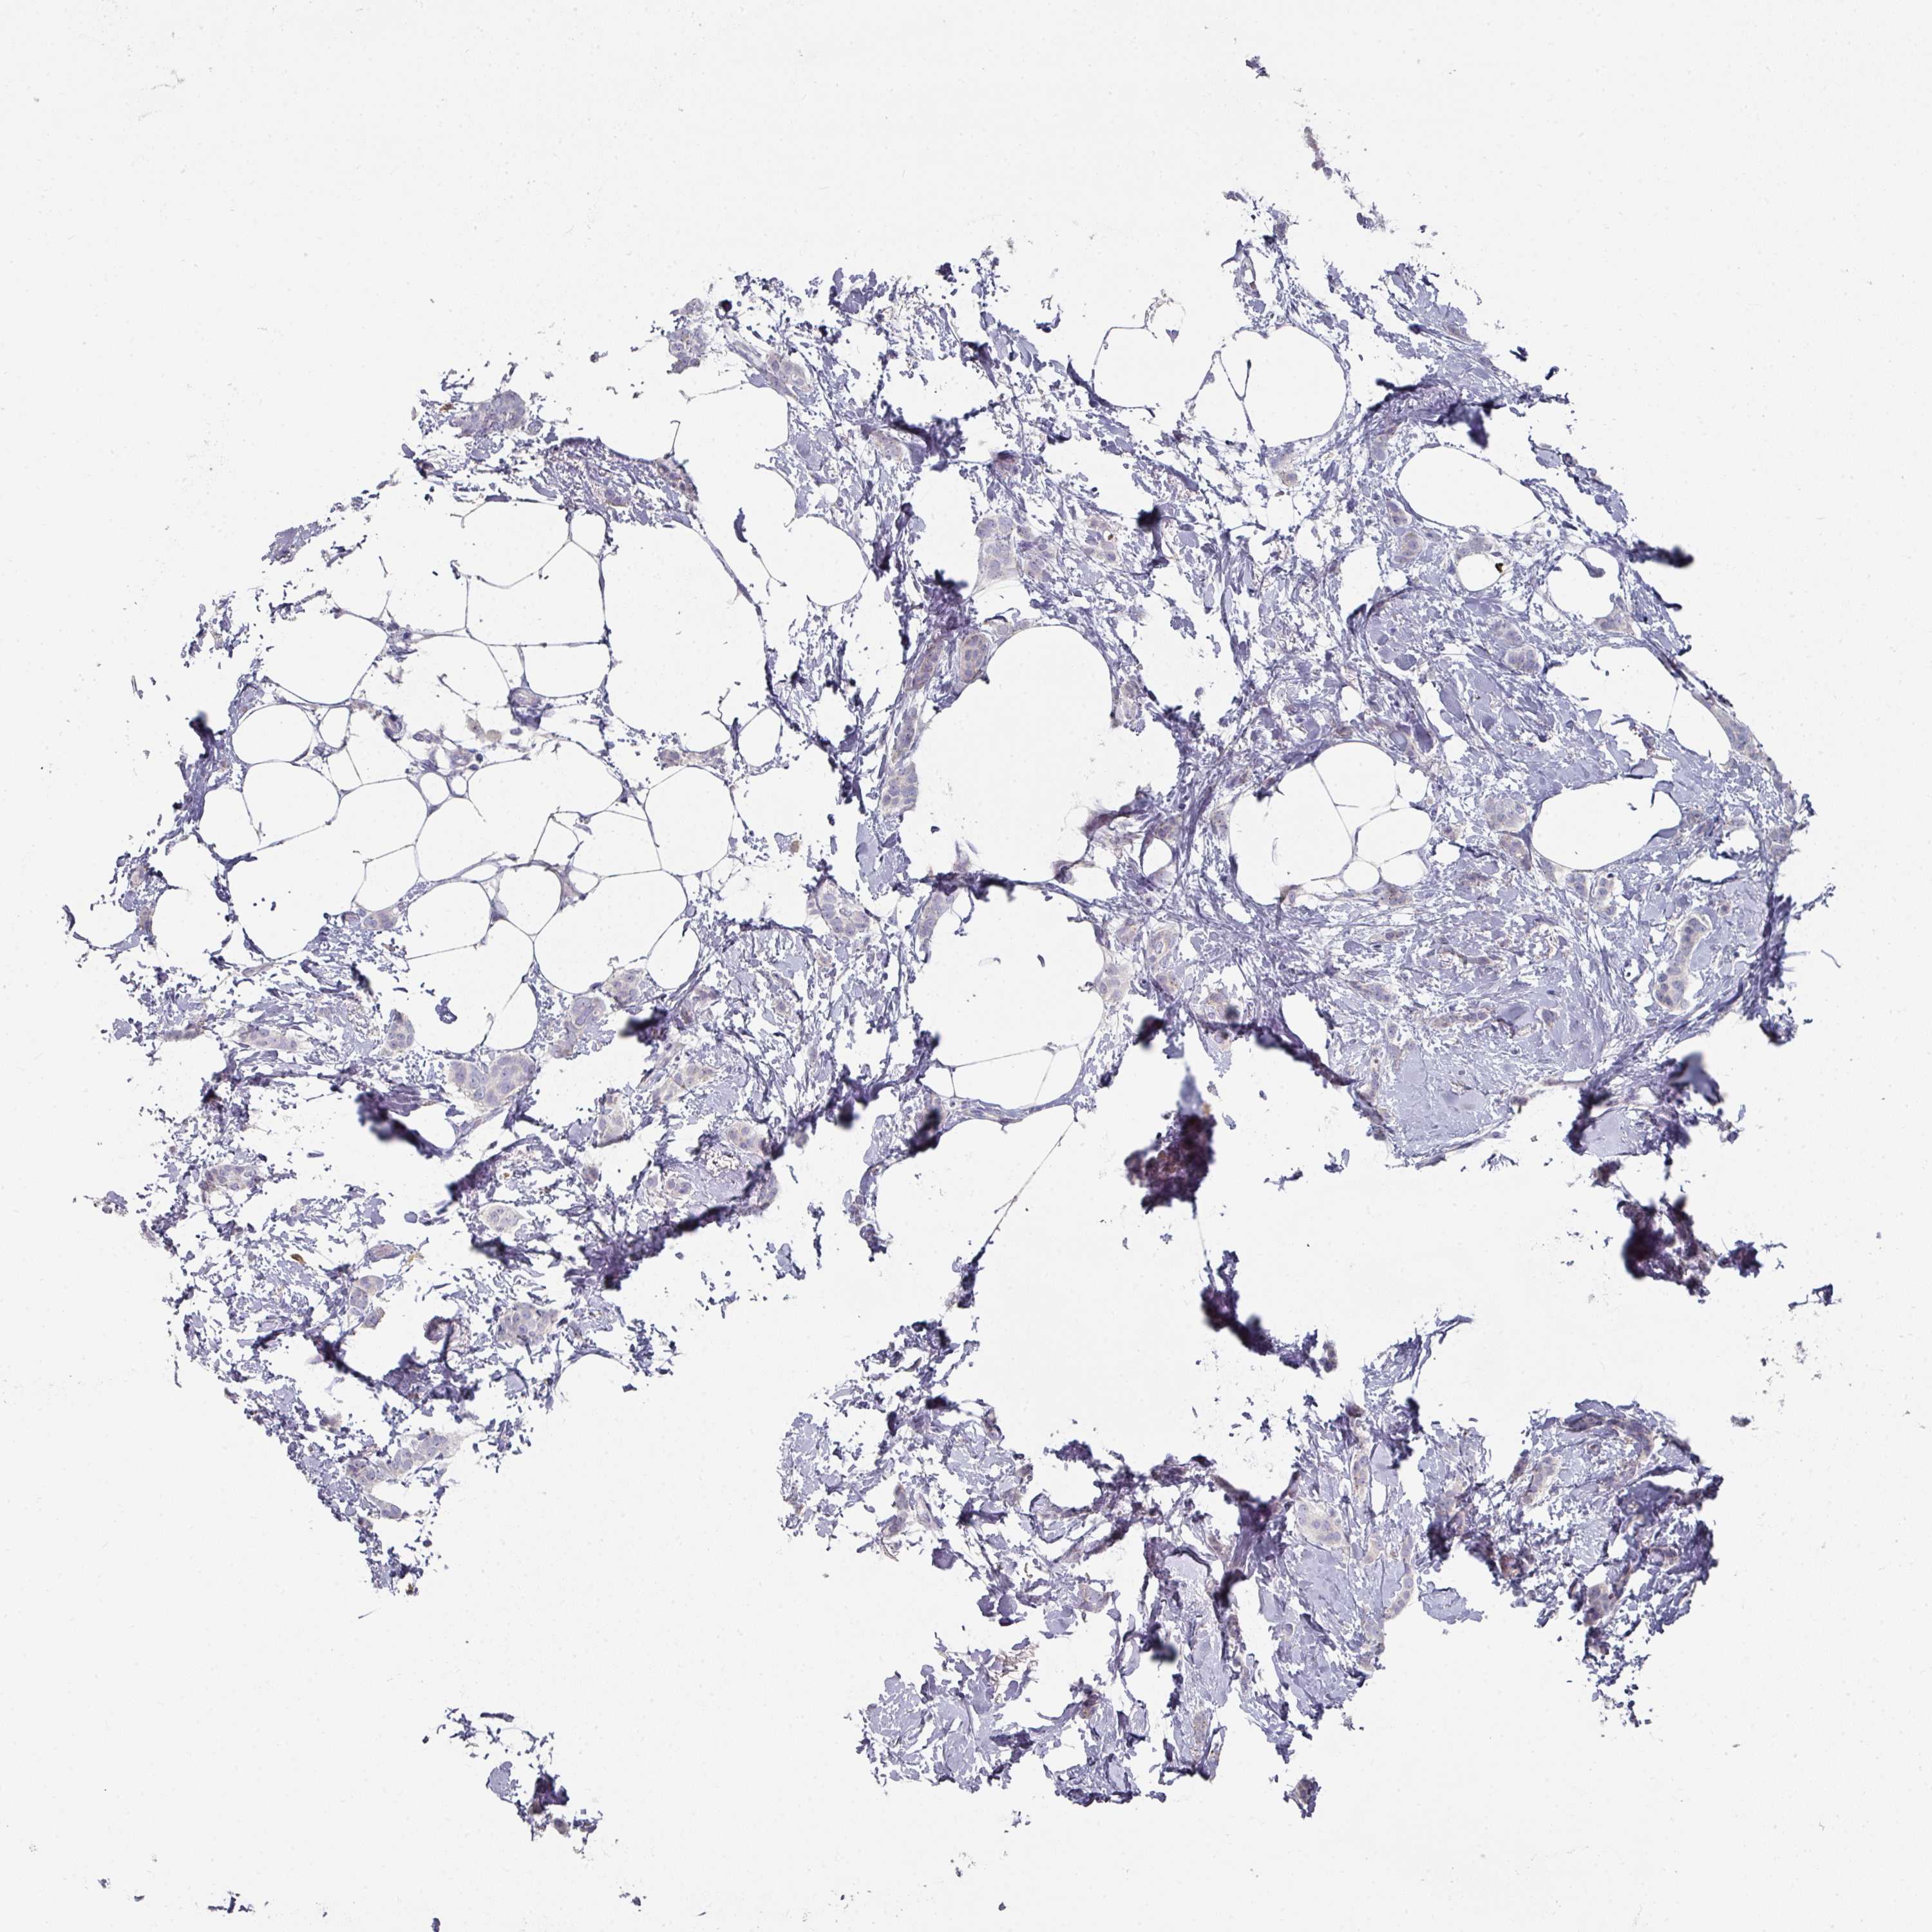

CANCER BREAST CANCER Show tissue menu

BRCA TCGA BRCA VALIDATION PROTEIN EXPRESSION